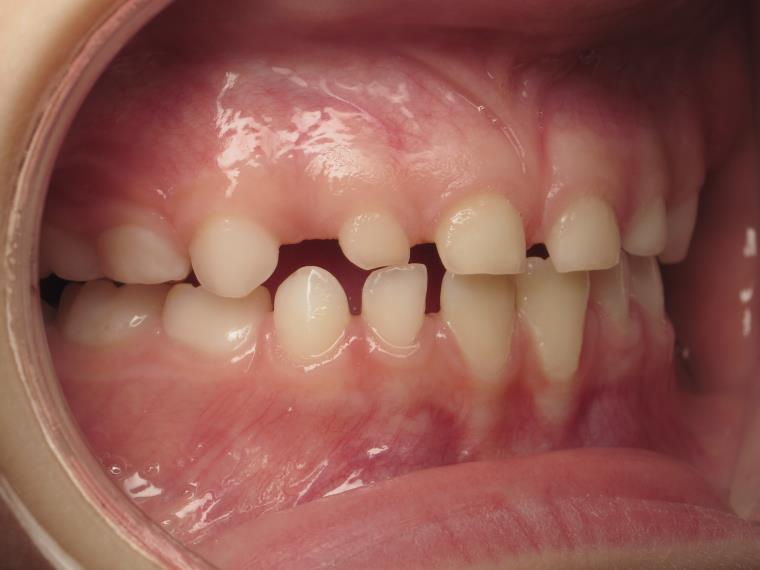

12 béance inversé droit 4 ans

inversion postérieur coté droit et espace entre les dents du haut et du bas (diastèmes)